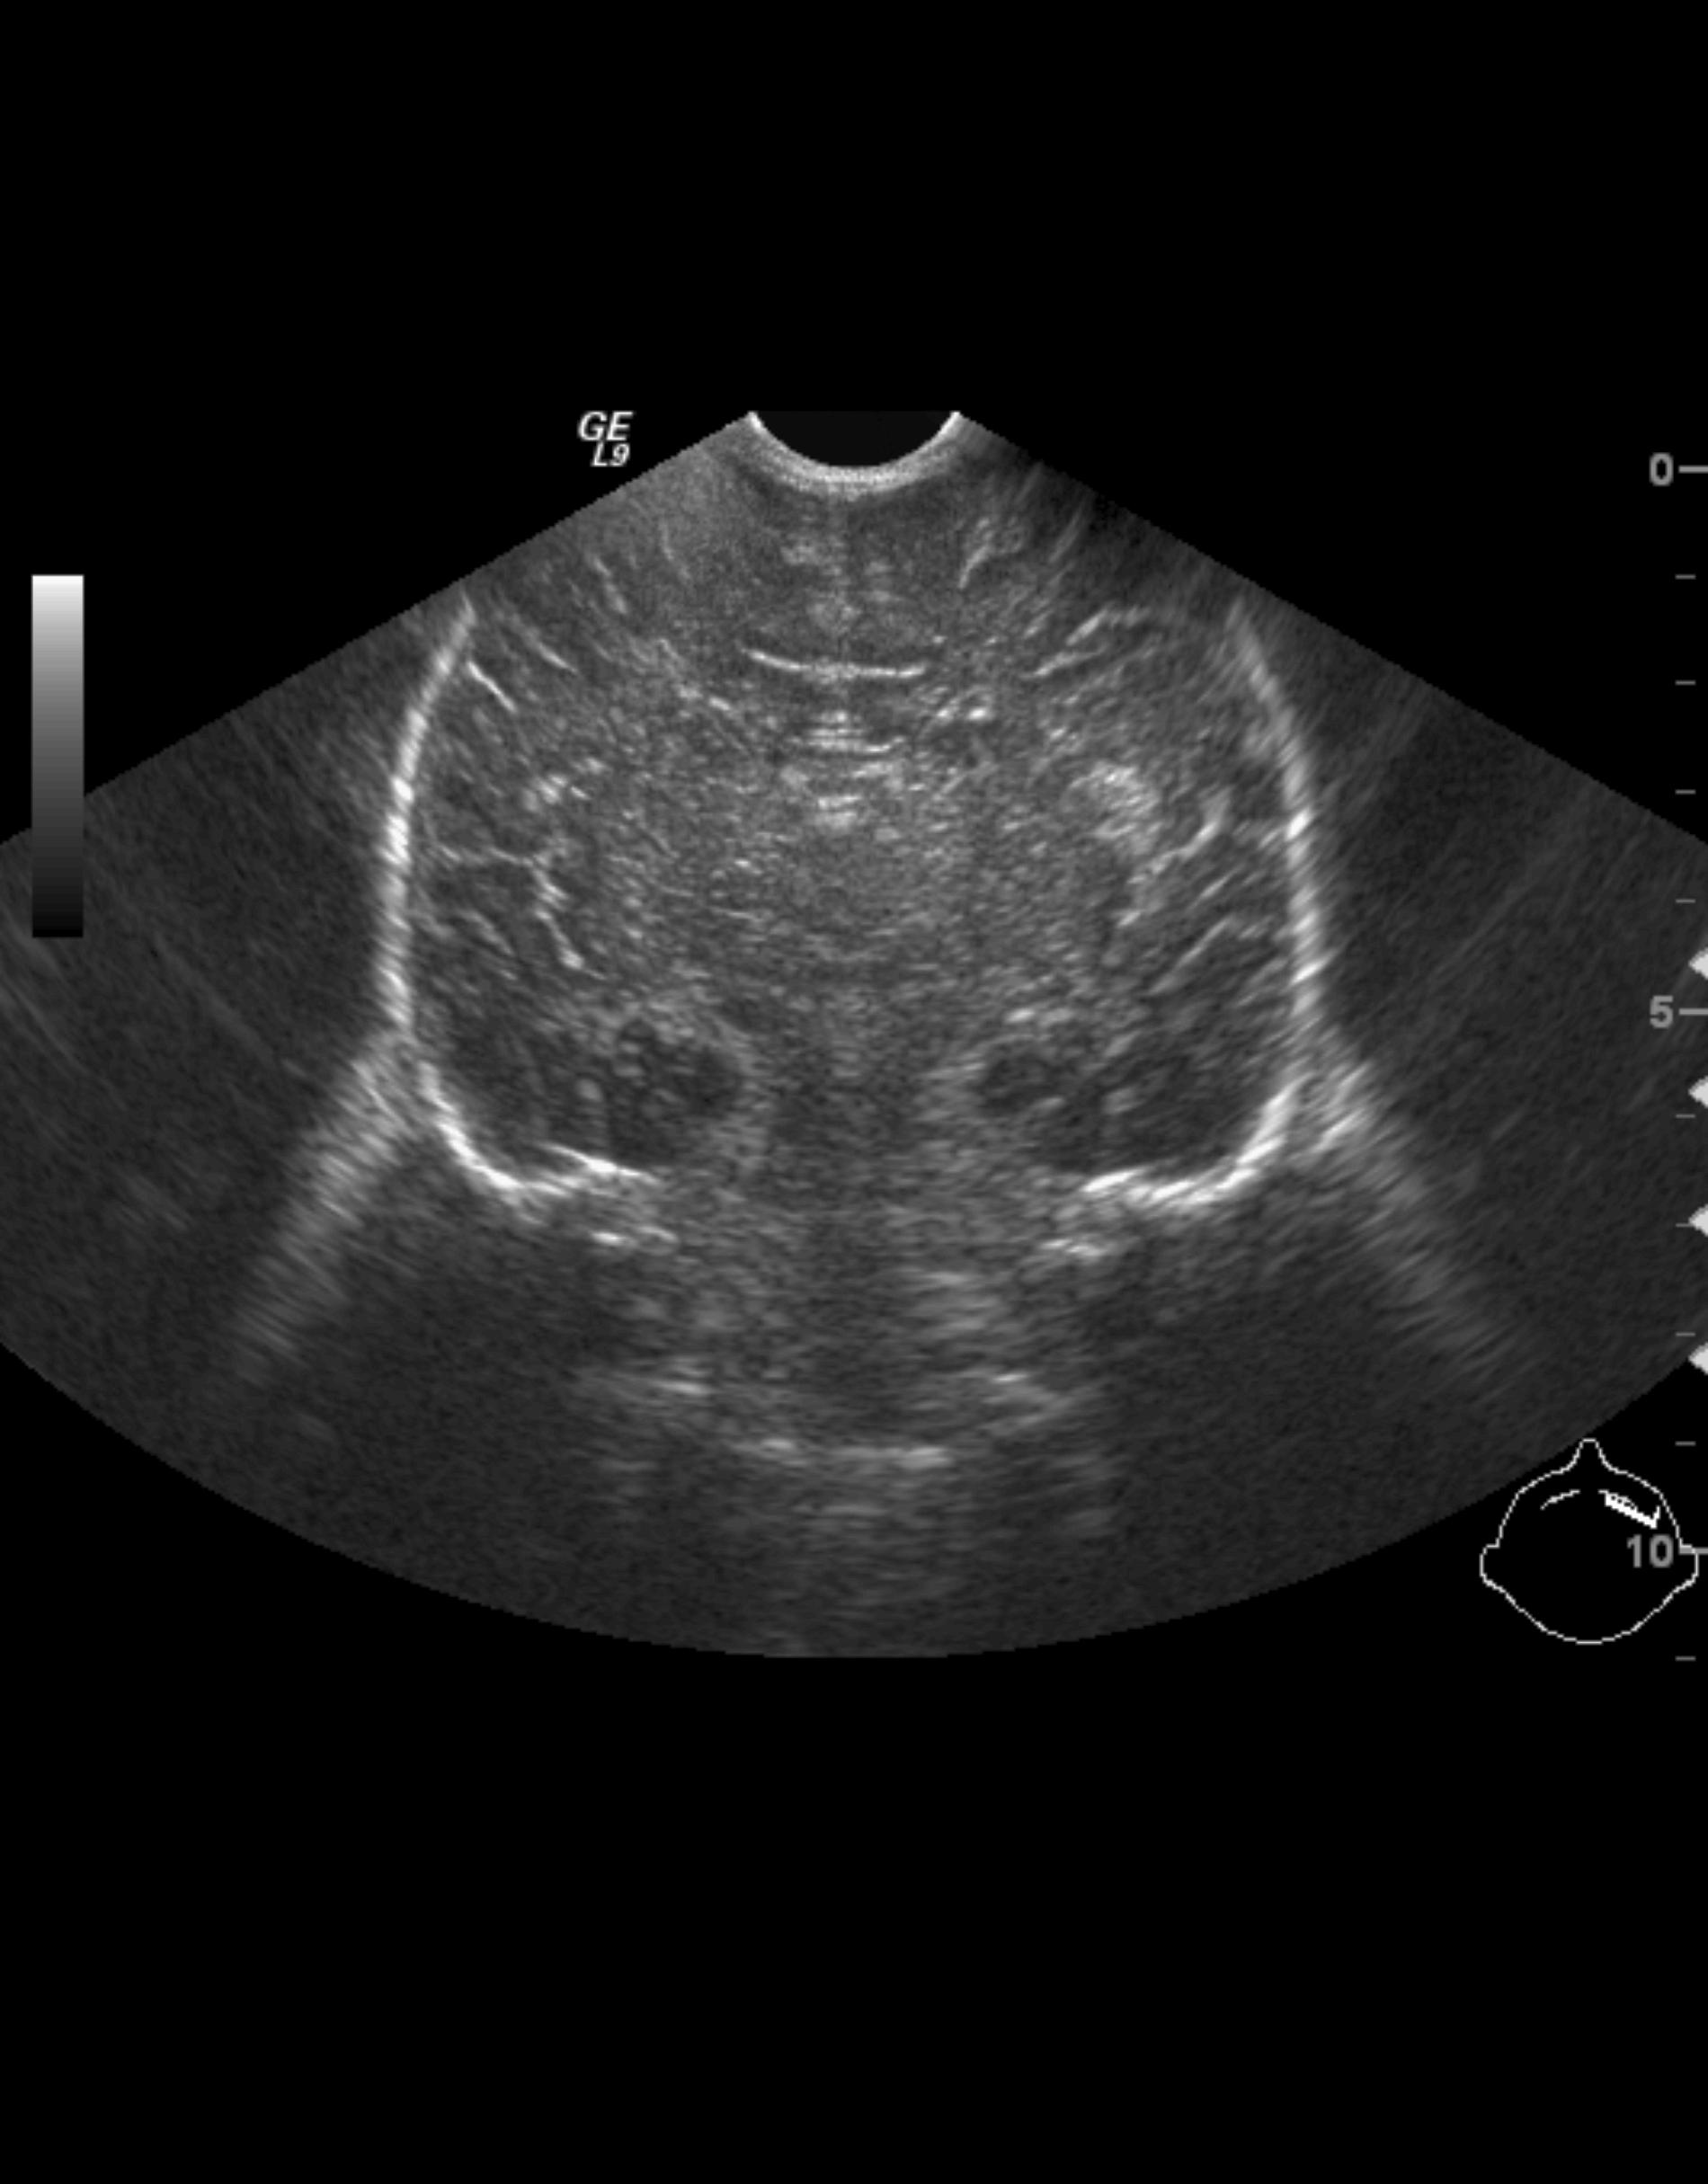

Cranial ultrasonography: is the first method of choice in brain parenchyma examinations. It can only be performed until the closure of the fontanelles (8-10months) (anterior and posterior fonatnelles, mastoidal and temporal region). Examinations require a high frequency convex transducer as well as a linear one. Vertebral ultrasound: can only be performed in the first 2-3 months of life until the closure of the vertebral arch, with a linear transducer.

30. a-d) Cranial ultrasound. Normal newborn brain. a-b. Coronal, c-d. Sagittal views.